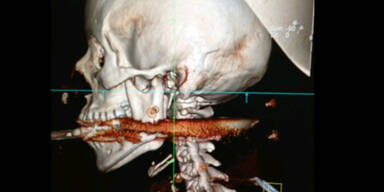

Der Ehemann löste das Gerät beim Säubern aus Versehen aus.

Wie durch ein Wunder hat eine junge Brasilianerin den Schuss mit einer Harpune überlebt, die sich durch ihren Kopf bohrte. "Man kann sagen, dass sie wieder auferstanden ist", sagte der Chirurg Marcelo Amaral am Donnerstag (Ortszeit) dem Fernsehsender TV Globo News nach einer zweistündigen Operation der 28-Jährigen. Elisangela Borborema Rosa war von dem Geschoß getroffen worden, als ihr Mann das Fischjagdgerät versehentlich beim Säubern auslöste.

Die Harpune sei durch den Rachen gedrungen, habe zwei Backenzähne zerschlagen und sei im ersten Halswirbel stecken geblieben, berichtete Amaral. Hätte das Geschoss nur "wenige Millimeter" weiter getroffen, wäre die junge Frau nun entweder "querschnittsgelähmt oder tot". Die Entfernung der Harpune sei sehr schwierig gewesen, weil in dem Bereich sehr viele Arterien verliefen, sagte der Arzt weiter.